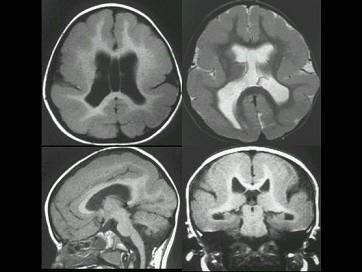

问题 患儿6岁,自1岁后多次癫痫发作,药物治疗疗效不明显。如图所示,最可能的诊断为?(?)

选项 A.巨脑回 B.脑裂畸形 C.灰质移位 D.无脑回畸形 E.无脑畸形

答案 D